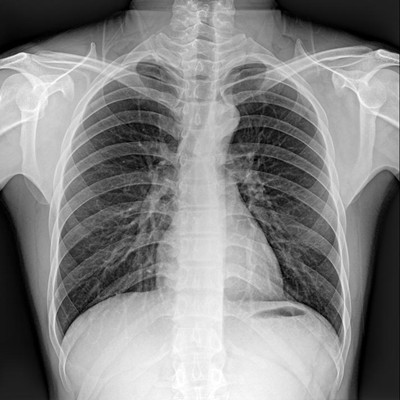

●大尺寸非晶硅平板探測器。

●非晶硅平板探測器,采用先進的制造工藝、性能更穩(wěn)定。

●探測器可以大范圍轉(zhuǎn)動,大尺寸有效探測面積,可滿足人體多部位攝影需求。